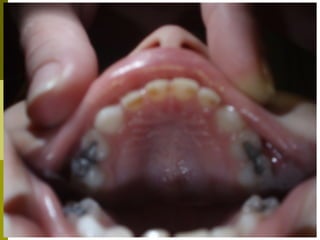

Μόνιμη οδοντοφυΐα 10 + ετών

 Παρακολουθούμε την ολοκλήρωση

αλλαγής δοντιών

 Ελέγχονται ορθοδοντικές ανωμαλίες

 Θεραπευτική αντιμετώπιση μονίμων

δοντιών

 Καλό προληπτικό πρόγραμμα,

εξατομηκευμένο